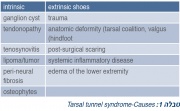

| 18:09, 12 במרץ 2016 | Tarsal tunnel1.jpg (קובץ) |  |

119 קילו־בייטים | Motyk | 1 | |